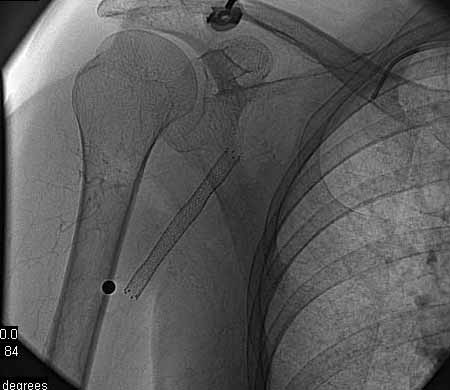

标题: DSA0091:肱动脉支架 [打印本页]

标题: DSA0091:肱动脉支架

女,66岁,右上肢无力.